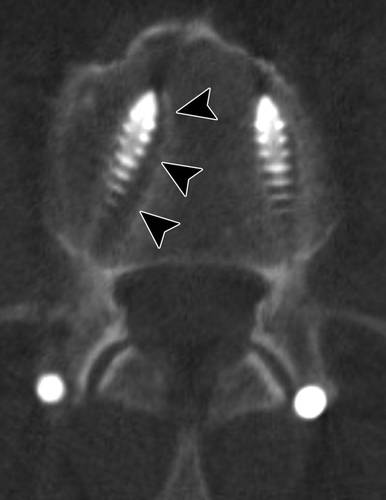

图12B-69岁的女性,因为腰痛和退行性变行L3-L4椎板切除术,然后出现尿失禁和下肢无力。轴向对比度增强T1加权脂肪抑制MR图像显示多个增强点和L4平面硬膜囊中的神经丛(箭头)聚集,增强图像表现与蛛网膜炎相符。